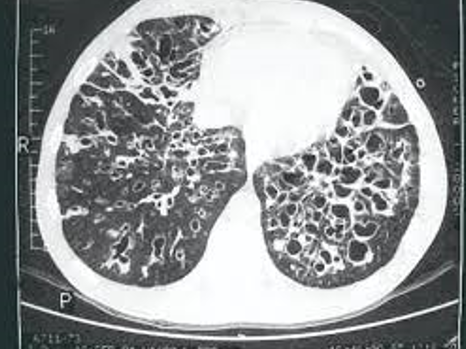

¿Qué te dice esto?

Patrón característico de neumopatía intersticial usual.

Patrón histológica Neumopatía intersticial usual

Panal de abeja